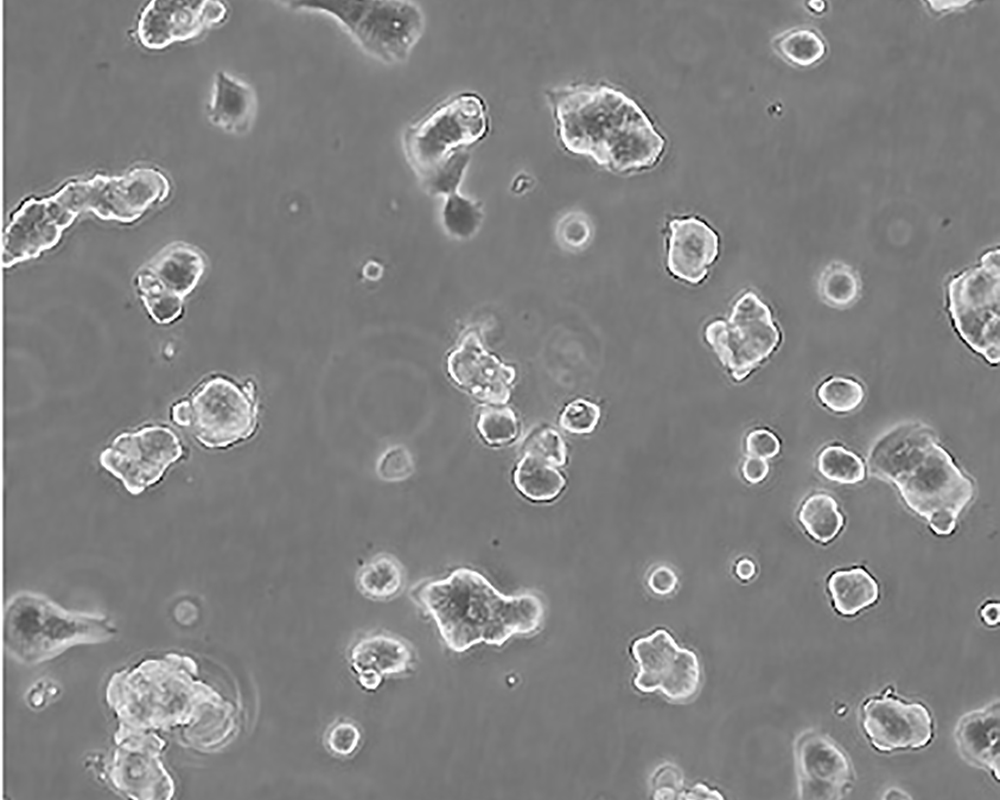

產品名稱 ZR-75-1 [ZR751]

中文名稱 人乳腺癌細胞

組織來源 浸潤性導管癌;腹水轉移;女性

生長特性 adherent

培養基 RPMI-1640+10% FBS+1% P/S

形態特征 epithelial

細胞描述 該細胞產生高水平的黏液素MUC-1 mRNA,低水平的MUC-2 mRNA,但不表達MUC-3基因;表達雌激素受體。